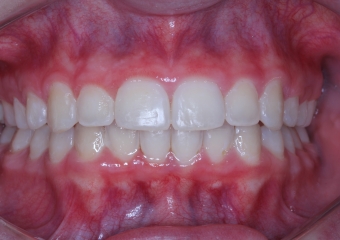

Sorriso final - 2019

Intra oral Final - 2019